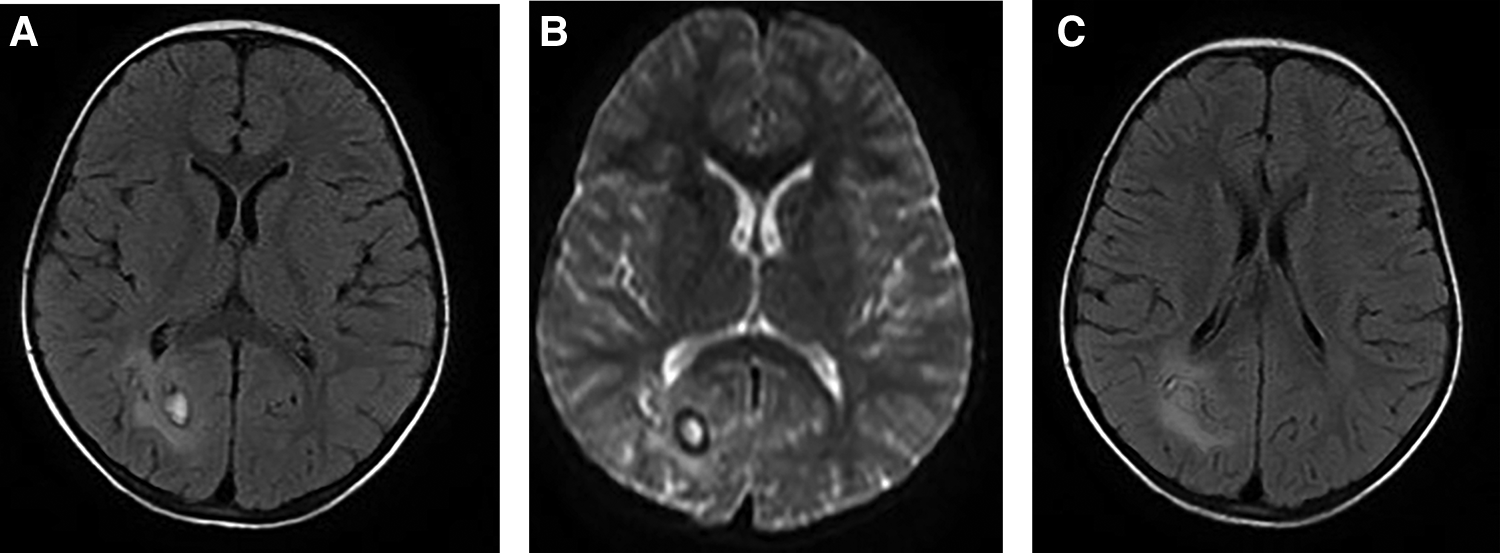

Figure 2

A 5-year-old girl visited our hospital due to limb movement disability. Brain MRI showed the lesion and its surrounding edema (A, B), and tunnel-like transitional signs (C).

On pulmonary CT, the most common findings were pleural effusion (68.9%) and alveolar exudation (64.4%) (Supplementary Material S3, Figure 1). Brain edema, nodules, and cerebral hemorrhage were found in children with cerebral paragonimiasis (Supplementary Material S3, Figure 2). Pleural effusion was one of the most important findings of ultrasonography. In addition, ultrasound examination also showed abdominal effusion, pericardial effusion, and subcutaneous nodules.

The diagnosis of paragonimiasis requires a combination of symptoms, signs, laboratory tests, risk factor, and other factors. In areas with high incidence of pneumofluke disease, the possibility of paragonimiasis should be considered in patients with multi-system symptoms. It is recommended that patients should be carefully enquired about their dietary habits, and etiological detection of Paragonimus should be conducted as soon as possible. If necessary, a tissue biopsy can also be used for establishing the diagnosis (14). CT or MRI may reveal migratory symptoms or the tunnel sign, which are related to the migration of Paragonimus larvae, and these findings may be useful to establish the diagnosis (13, 14).

All children were treated with praziquantel and their symptoms improved after treatment. For cerebral paragonimiasis, surgical intervention is necessary if signs of cerebral herniation occur (14). In our study, four children with cerebral paragonimiasis were treated with praziquantel for up to 12 weeks. After treatment, headache, vomiting, and other symptoms were relieved, but a 5-year-old girl experienced sequelae (limb motor disability) due to persistence of cerebral tissue injury. In addition, patients with cerebral paragonimiasis may experience other sequelae, such as speech disorders and seizures (3, 8). Cerebral paragonimiasis is one of the most serious types of paragonimiasis, and it can cause headache, vomiting, movement disorders, seizures, and even death due to intracranial hypertension (3, 15, 16). All four children had symptoms, such as headache and intracranial hypertension, which were consistent with a previous study (14). The main pathogenic mechanism of cerebral paragonimiasis is direct and indirect damage to the brain tissue. Paragonimus larvae migrate to the brain tissue, directly destroying the local brain tissue. They can damage different parts of cerebral tissue, and the clinical symptoms also vary. Indirect injury is mainly caused by local brain edema, followed by intracranial hypertension. At this point, patients may present with symptoms of intracranial hypertension, such as headache, vomiting, papilledema, and hypertension (14).